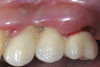

Fig 9. Treatment of peri-implant mucositis: plaque accumulation and mucosal inflammation.

Figure 9